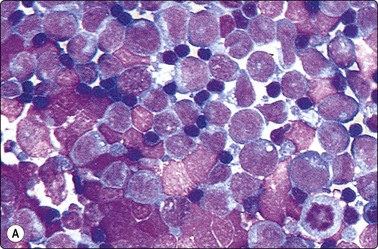

Thin watery samples are processed by centrifugation in a cytocentrifuge. Millipore or Nucleopore filtration is an alternative but has been less satisfactory in our hands. Some laboratories prefer to rinse needles and syringes routinely with saline or with a fixative, which is then centrifuged or filtered onto slides.11,12 More recently, the ThinPrep technique developed for gynecological cytology has been increasingly applied also to FNB specimens.13-16 These techniques offer alternative solutions to the frequent problem of suboptimal samples received from distant sources, when the laboratory has no control over the biopsy procedure. However, the ThinPrep technique has its specific problems, and established diagnostic criteria may have to be redefined for FNB samples.17,18 In our opinion, direct smears expertly prepared by an experienced cytopathologist remain the optimal basis for FNAC diagnosis available today, and our first priority is to perfect this technique. ThinPrep preparations are a valuable supplement, particularly for immunocytochemical staining (see below).

Monolayered smears with optimal cell preservation are particularly important in the diagnosis of malignant lymphoma. For lymph node aspirates, we recommend that a cell suspension be prepared in addition to direct smears. Hank’s balanced salt solution with the addition of 10–20% fetal calf serum is ideal for this purpose. The suspension is spun on the cytocentrifuge at low r.p.m. Dilution may be necessary to achieve optimal dispersion of cells on the slide and to avoid clumping (Fig. 2.13). A number of slides can usually be made from one aspirate to allow immunocytochemical studies. Further details on techniques suitable for lymph node samples are given in Chapter 5.

image image

Fig. 2.13 Cytocentrifuge smears of lymphoid cells

Cell suspension in Hank’s balanced salt solution of FNB sample of cells from lymphoma; cytocentrifugation smears. (A) Undiluted specimen; (B) Optimal dilution (MGG, HP).